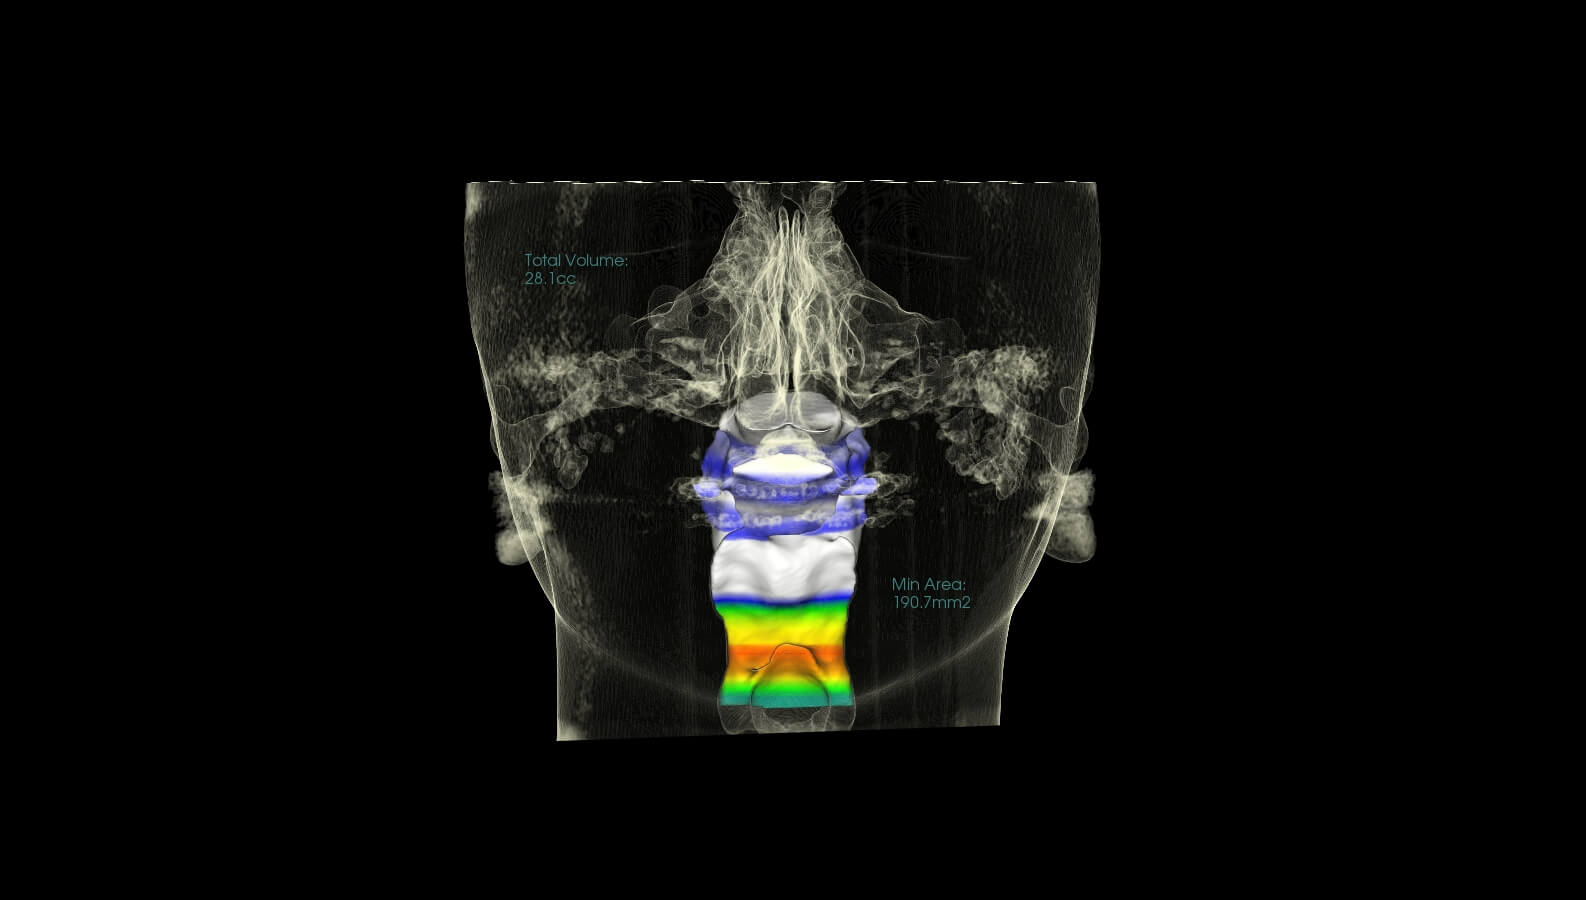

These are before and after CBCT images of patients treated at Marlo A. Miller, DDS. Both struggled with enlarged adenoids and tonsils. An adenotonsillectomy, or removal of the tonsils, was performed based on Dr. Miller and an ENT recommendation. This procedure alleviates airway restriction contributing to breathing/sleep issues and reduced overall health and wellness. Dr. Miller also did some minor Upper and Lower expansion. There is a Significant airway change in both patients, and both report sleeping better and feeling better overall.